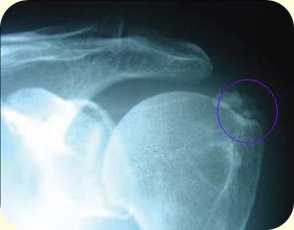

Диагноз ставиться после тщательного выяснения жалоб, анамнеза, осмотра и физикального исследования, анализа рентгенографических признаков кальциноза. Диагноз кальцифицирующего тендинита плеча подтверждается рентгенологически по наличию кальциноза сухожилия. Этот признак не всегда бывает легко обнаружить. Для его выявления выполняются снимки плечевого сустава в прямой проекции при нейтральном положении, а также наружной и внутренней ротации. На ранней стадии депозиты бывают плотными и хорошо определяются.

![]() | ![]() |

рентгенограммы плечевого сустава, кальцификаты обведены кружком